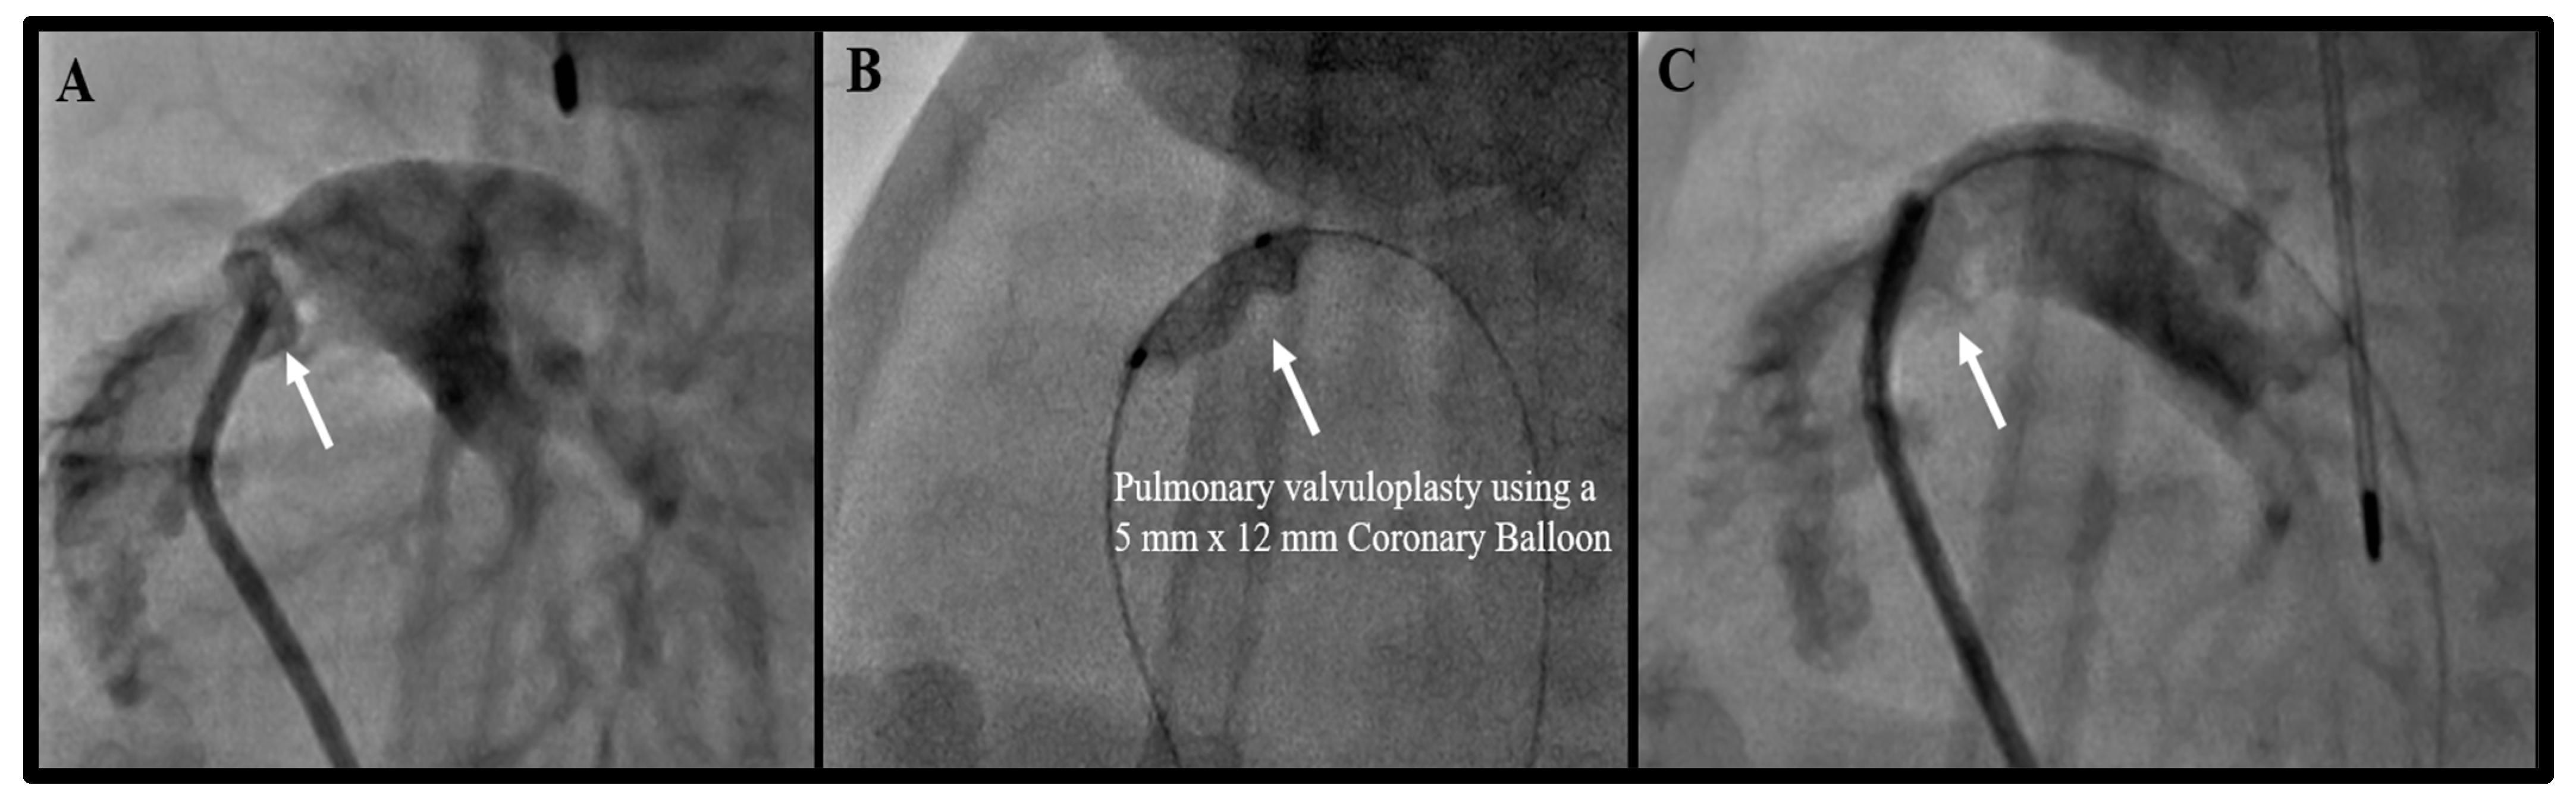

| 2. Pulmonary Valvuloplasty | 9 |

| 2. Pulmonary Valvuloplasty *∂€ | 9 | 0 | 0 | 6 |